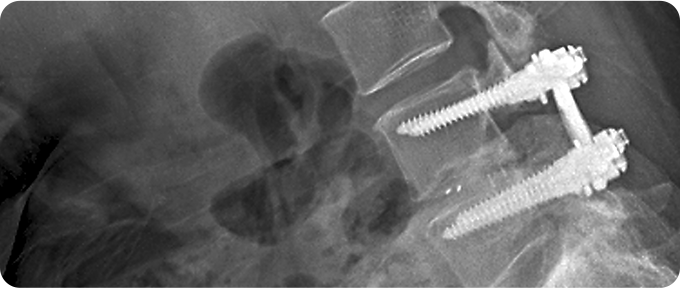

척추 고정술 사진

척추 고정술

척추가 불안정하거나 심하게 전위된 경우 사용하는 수술적 치료법입니다. 금속 나사나 막대를 이용해 손상된 척추를 고정하여 척추의 안정성을 회복하고 추가 손상을 방지합니다. 이 방법은 신경 압박을 해소하고 통증을 줄이는 데 효과적이며, 수술 후 재활과 관리를 통해 정상적인 척추 기능을 회복할 수 있습니다. 고정술은 전문의의 판단에 따라 최적의 치료법으로 선택됩니다.